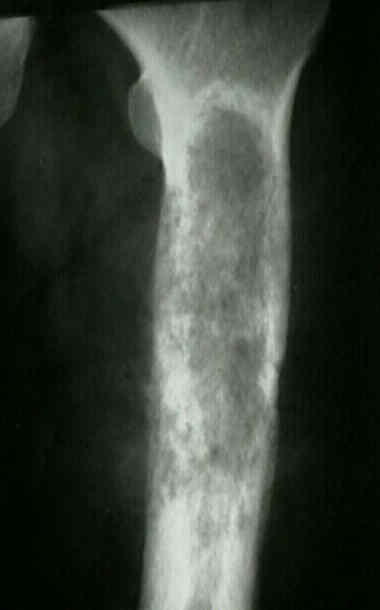

Orthopedics

単発性骨嚢腫

上腕骨・大腿骨の近位骨幹端、踵骨

10-20代に多い

非骨化性線維腫

大腿骨遠位・脛骨近位の骨幹端

軟骨芽細胞腫

上腕骨近位・脛骨近位・大腿骨両端の骨端線閉鎖前の骨端に好発

線維性骨異形成

大腿骨・脛骨の骨幹

思春期早発症を合併するものはAlbright syn.←ほとんどが女性